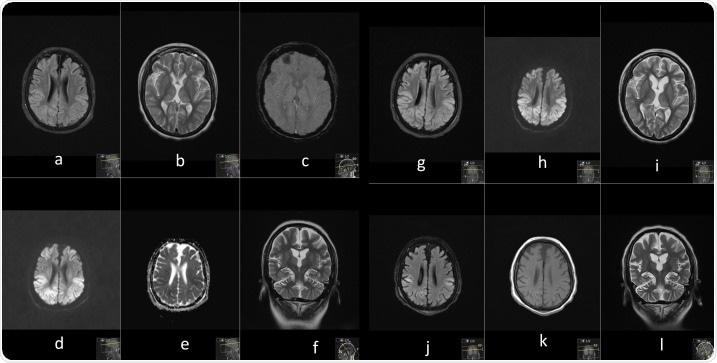

MRI

Serial contrast enhanced MRI brain performed prior to illness and at 3 time points during current illness. Image Credit: https://www.seizure-journal.com/article/S1059-1311(20)30362-9/fulltext

A time-dependent brain MRI - before illness, during illness, repeat, and follow-up - showed widespread bilateral cortical, cerebellar and thalamic signal change and swelling; persistent multifocal areas of neuroparenchymal signal change; and evolving laminar necrosis in the areas previously affected. Further episodes of suspected seizures persisted intermittently.